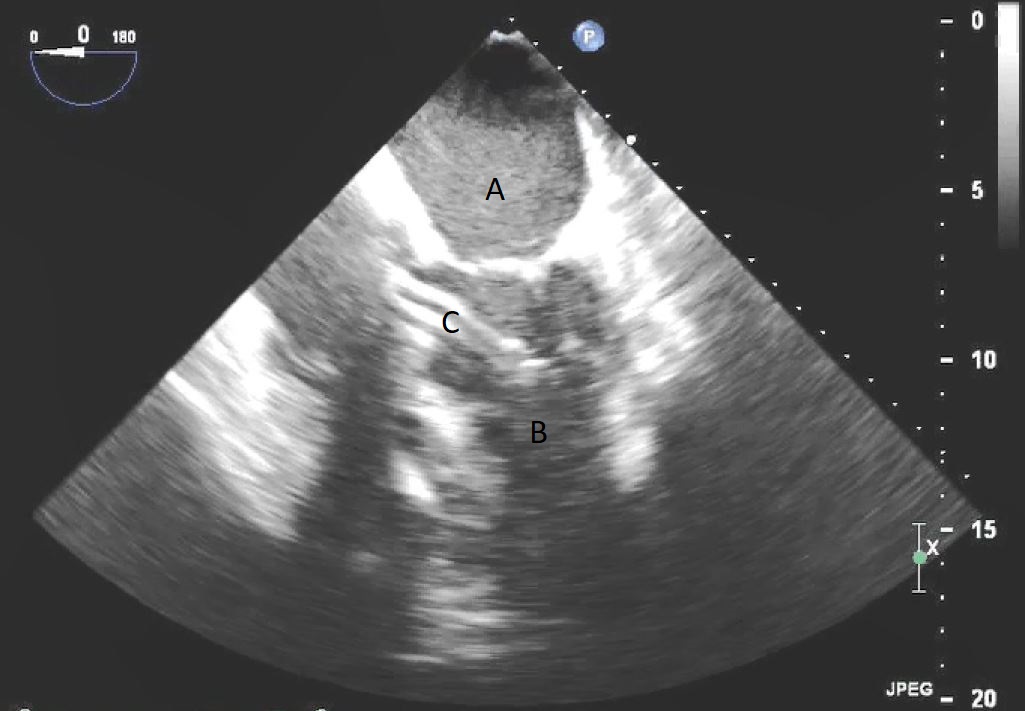

Fig. 7.A parasternal long axis view on a transthoracic echocardiogram. The distance from the Impella inlet to the aortic valve is measured and noted to be 3.9 cm. (A) LV Cavity. (B) Impella. (C) Ascending aortic root.